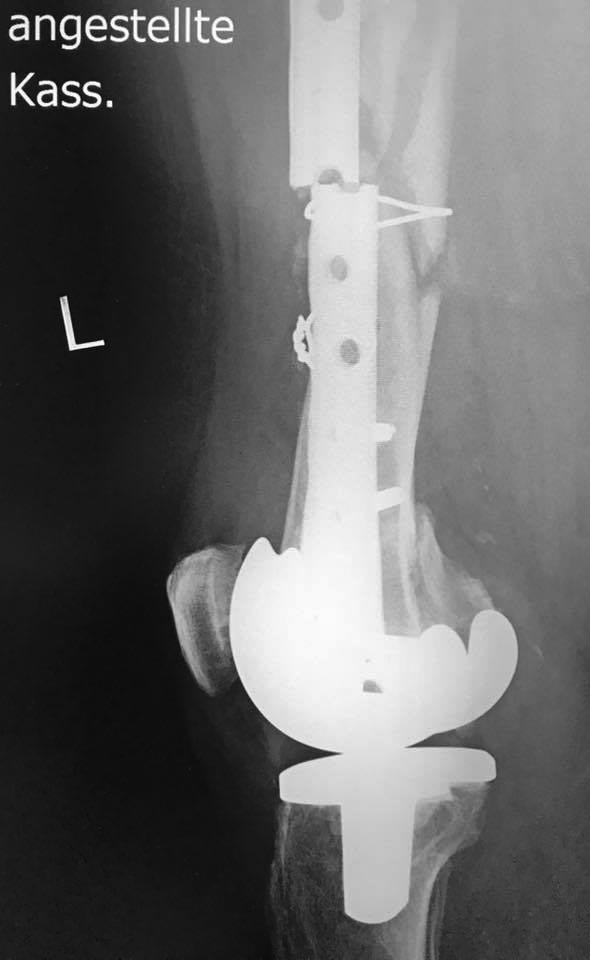

Re: Перипротезный перелом дистального отдела бедра

Случившийся перелом - предполагаемое течение процесса. Сейчас надо удалить пластину, винты Выполнить лучше ретроградный интрамедуллярный остеосинтез (можно бедренным Деост) т.к. проксимальная часть имеет больший диаметр, а значит конструкция будет стабильнее. Конечно в дистальный части несколько блокирующих винтов. Желательно перед операцией уточнить межмыщелковое расстояние у бедренного компонента эндопротеза и определиться с диаметром стержня. Дополнительная пластина не будет способствовать формированию параоссальной мозоли.оптимальнее интрамедуллярный остеосинтез дополнить костной пластикой

Реостеосинтез такой же пластиной. Костная пластика, убрать серкляж, и винты в отмеченных позициях тоже, то есть увеличить зону " работы" пластины. Или гвоздь.